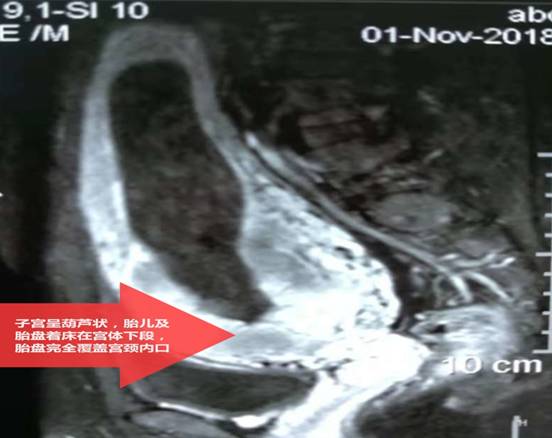

||